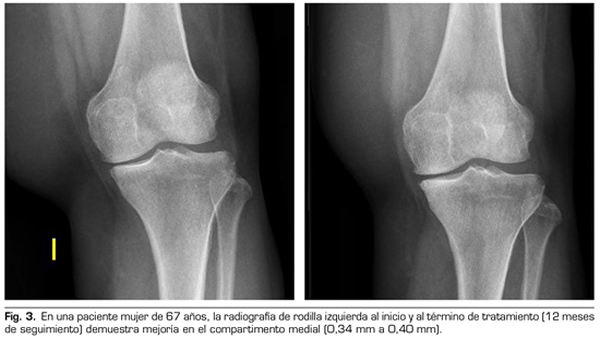

Con respecto a las variables radiológicas, al valorar a 53 de los 115 pacientes que cumplieron un año de seguimiento después del tratamiento con ozono, se observó que el compartimento interno aumento significativamente de 4,12 ± 1,41 mm a 4,4 ± 1,35 mm (p = 0,0008) y el compartimento externo aumentó de 6 ± 1,37 a 6,16 ± 1,4 mm (p = 0,0753) (Tabla II). Se presentan 2 casos clínicos como muestra del cambio radiológico en los compartimentos interno y externo (Figuras 2 y 3).

Para la evaluación radiográfica de la articulación tibiofemoral medial y lateral, se realizaron radiografías bilaterales anteroposteriores, con ambas piernas apoyadas y completamente extendidas, en carga según protocolo estandarizado (9). Todas las imágenes radiográficas se adquirieron digitalmente mediante un sistema de comunicación de archivo de imágenes (PACS). Se evaluó a 53 pacientes de los 115 que cumplieron un año de seguimiento tras la primera infiltración. Se midió la distancia femorotibial en la radiografía en los compartimentos medial y lateral en la distancia percibida como la más estrecha del espacio articular, y utilizando el programa de medición PACS. Todas las evaluaciones fueron llevadas a cabo por un solo autor, con el fin de reducir la variación interobservador, cuyo coeficiente de variación para medidas repetidas es 3-8 % (9,10).